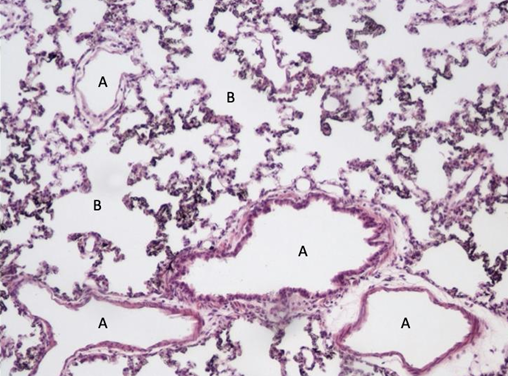

płuca nr 409

oskrzeliki nabłonek jednowarstwowy walcowaty urzęsiony????

pęcherzyki płucne zbudowane z nabłonka jednowarstwowego płaskiego (wyróżniamy pneumocyty 1 i 2 (urzęsione uwypuklone) rządu